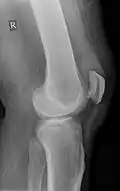

An x-ray demonstrating quadriceps tendon rupture. Note the abnormal angle of the patella and soft-tissue swelling marked by the arrow.